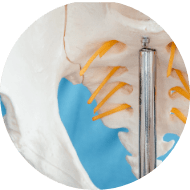

HIP REPLACEMENT

When hip pain is rooted in advanced arthritis or severe joint deterioration, hip replacement will be the go-to treatment. This procedure involves substituting the compromised joint with an artificial implant, effectively minimising pain and reinstating functional mobility.

FEMORAL OSTEOPLASTY

This is a procedure where your femur is surgically altered. This procedure involves reshaping the femur to mitigate impingement, thus facilitating smoother joint movement and reducing discomfort.

PERIACETABULAR OSTEOTOMY

Commonly performed on those with specific hip conditions such as shallow hip sockets (acetabular dysplasia), periacetabular osteotomy repositions the socket to fit better with the femoral head. This adjustment can promote better hip health and joint coordination.